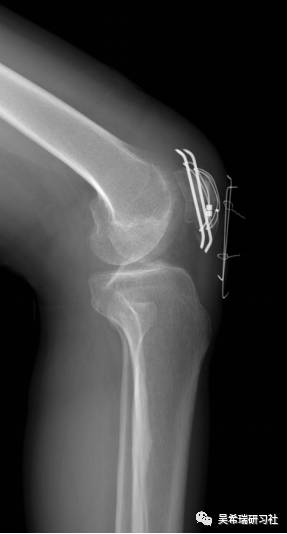

平台骨折手术后继发感染

TIPS:内固定感染常见病不要轻易做皮瓣,感染情况下不可深部骨感染、窦道用水泥切实可行多数皮肤没有缺损,肿胀消退后可以牵张闭合